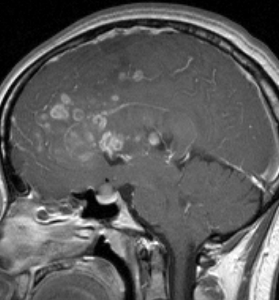

若い成人です,認知機能障害で発症しました。この画像を見るからに悪性神経膠腫,少なくともグレード3のグリオーマであることは明白です。しかし,グレード4膠芽腫あるいはグレード3退形成性星細胞腫にしては腫瘍周辺浮腫が軽すぎます。ですから,グレード3の退形成性乏突起膠腫 AO かも。認知機能の回復と温存を考量して,脳梁損傷と前交連損傷を避けて,右上前頭回と帯状回腫瘍を摘出しました。

左は術後のT1強調ガドリニウム増強像で,残存腫瘍がわかります。この腫瘍に対してICE (IFO/CDDP/VP-16) 化学療法を1コースしました。右側のMRIが1ヶ月後の画像です。このように1p/19q欠失のある退形成性乏突起膠腫は,化学療法感受性がとても高い悪性グリオーマです。ですから,手術で後遺症を残さないように,勢い込んで腫瘍を摘出しようとしないことが大切です。光顕診断はAOで,後々の解析で1p/19q codeletion でした。